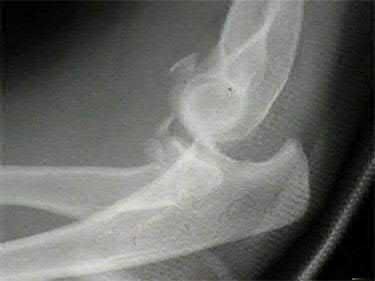

Question 2:

A 28-year-old male sustains a severe hyper-dorsiflexion injury to his ankle in a motor vehicle accident, resulting in a Hawkins Type III talar neck fracture. Which of the following arteries provides the predominant blood supply to the body of the talus, placing it at significant risk for avascular necrosis in this injury?

Correct Answer: Artery of the tarsal canal

Explanation:

The artery of the tarsal canal, which is a branch of the posterior tibial artery, provides the dominant blood supply to the talar body. In a Hawkins Type III fracture (talar neck fracture with subtalar and tibiotalar dislocation), the blood supply from the artery of the tarsal canal, the artery of the sinus tarsi, and capsular vessels are disrupted, leading to an avascular necrosis (AVN) rate approaching 100%.